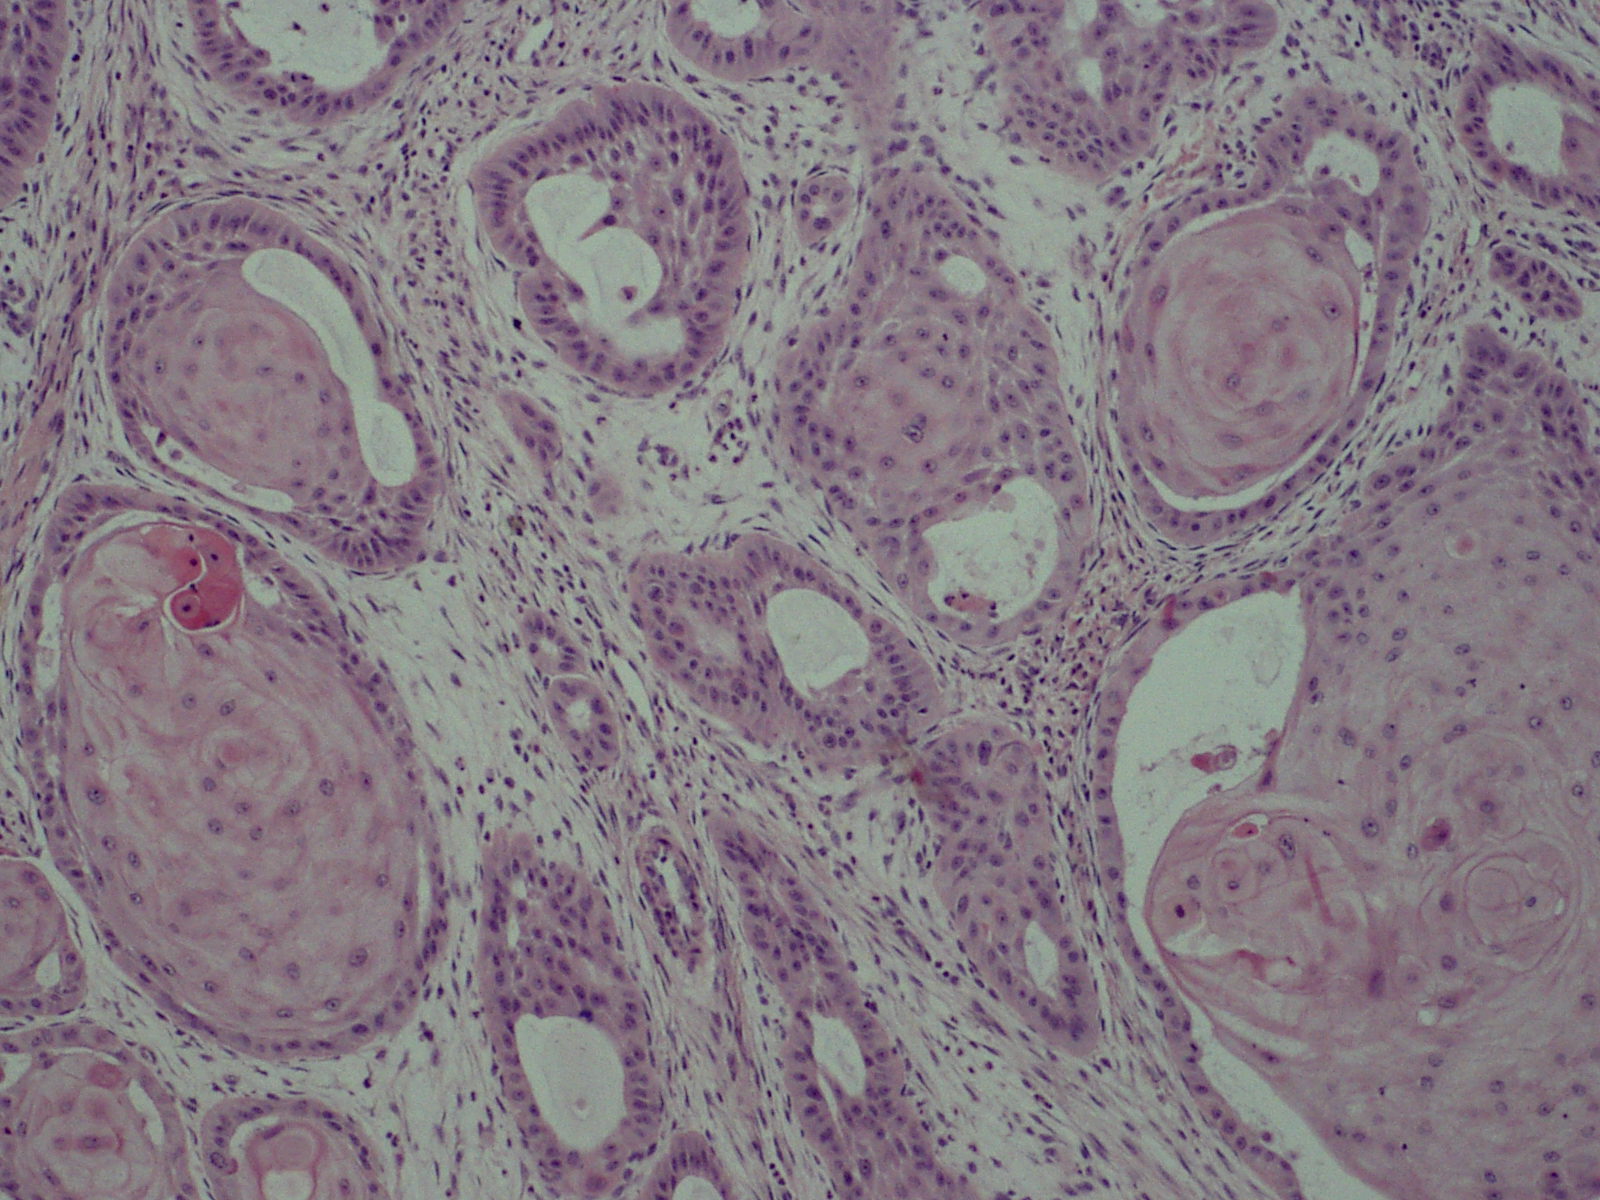

편평상피세포암(SCC)은 상피 계통의 암 줄기 세포가 반복적이고 제어되지 않게 분열하면서 시작된다.[19][20][21] 이 암은 신체 여러 부위를 덮고 있는 편평한 세포인 편평 상피 세포에서 발생하며, 그 중 일부는 각질 세포이다. 암세포가 축적되면 비정상 세포의 미세한 초점이 생기는데, 초기에는 기원 세포가 있던 조직 내에 국한된다. 이러한 상태를 편평상피세포 상피내암종이라고 한다.

병변이 성장하여 인접 구조를 파괴하고 침투하면 "침윤성" 편평상피세포암이라고 한다. 침윤성 암은 다른 장기로 퍼져 전이를 일으킬 수 있다.

병력, 신체 검사 및 의학 영상은 편평상피세포암을 시사할 수 있지만, 일반적으로 조직병리학적 생검을 통해 진단을 확정한다. TP63 염색은 편평상피세포암의 주요 조직학적 표지자이다. 또한 TP63은 편평 세포의 정체성을 확립하는 데 필수적인 전사 인자이다.[18]

- 반지세포 편평상피세포암(때로는 반지세포 편평상피세포암으로 표현됨)은 각질로 구성된 동심원과 현저하게 확장된 소포체에 해당하는 큰 공포가 특징인 조직학적 변이형이다.[25] 이러한 공포는 세포 세포 핵을 세포막 쪽으로 급격하게 이동시킬 정도로 확장되어 현미경으로 볼 때 세포가 독특하게 "반지"와 유사한 모습을 보인다.